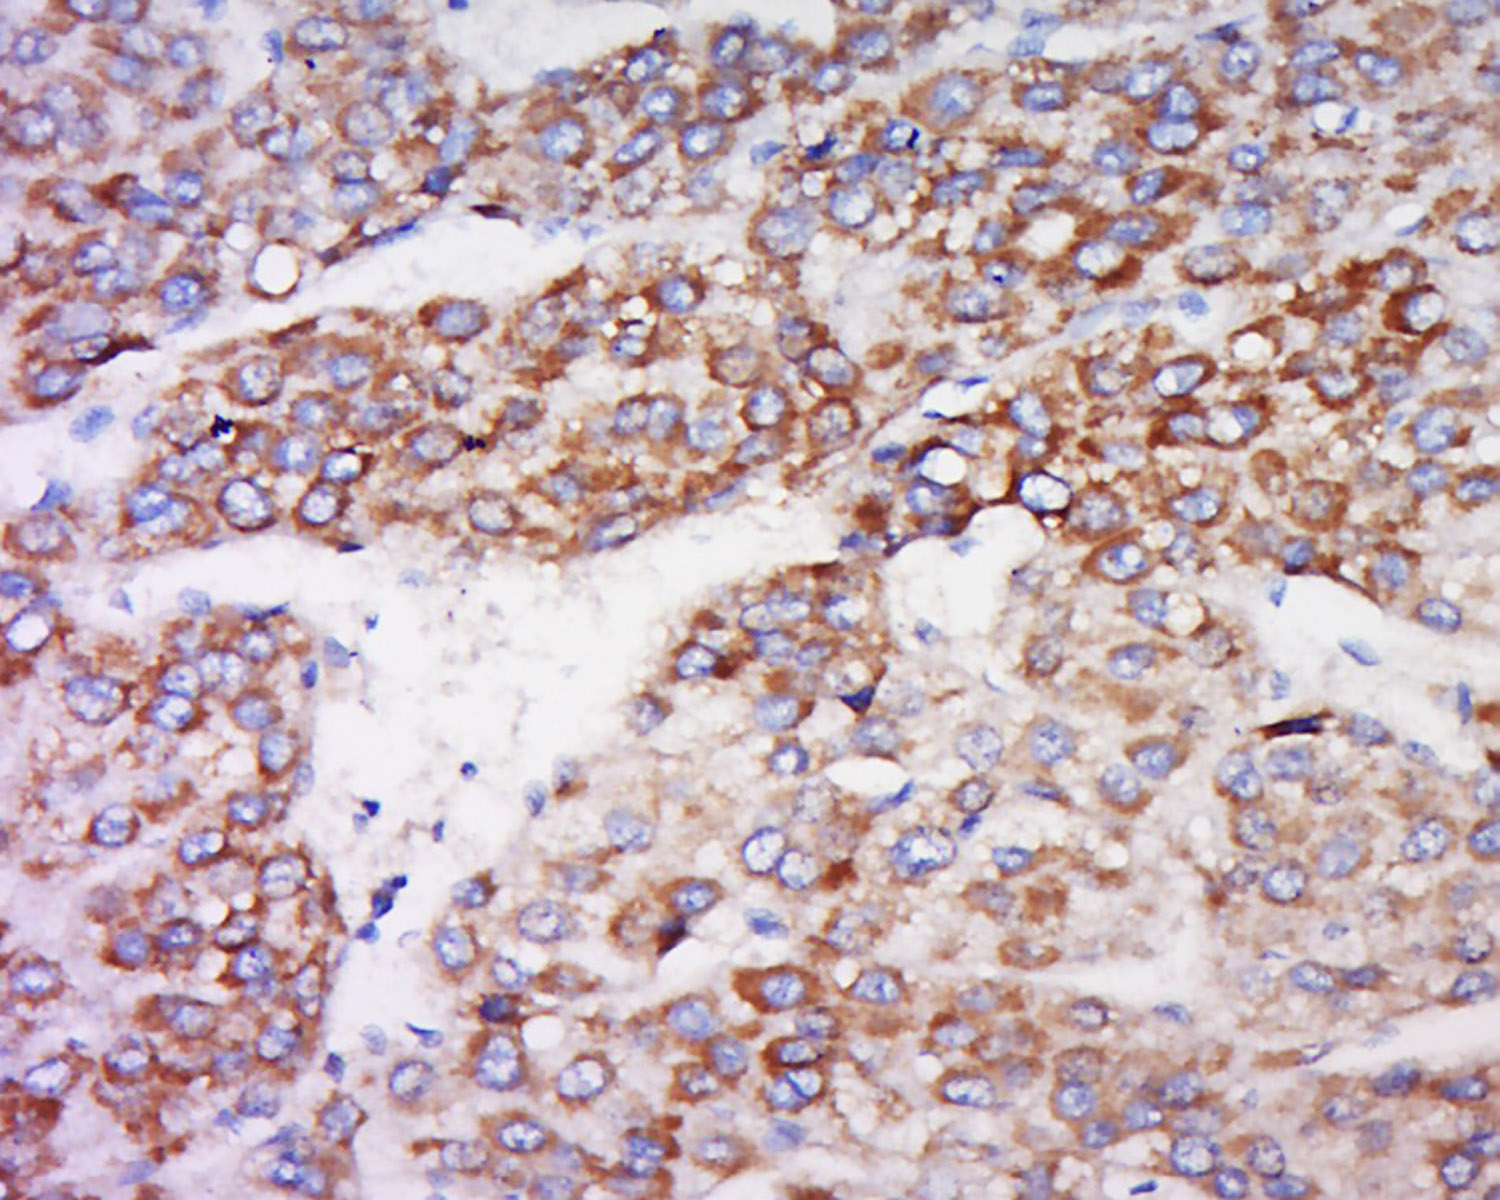

Tissue/cell: human liver cancer; 4% Paraformaldehyde-fixed and paraffin-embedded; Antigen retrieval: citrate buffer ( 0.01M, pH 6.0 ), Boiling bathing for 15min; Block endogenous peroxidase by 3% Hydrogen peroxide for 30min; Blocking buffer (normal goat serum,C-0005) at 37℃ for 20 min; Incubation: Anti-INDOL1 Polyclonal Antibody, Unconjugated(bs-16640R) 1:500, overnight at 4°C, followed by conjugation to the secondary antibody(SP-0023) and DAB(C-0010) staining